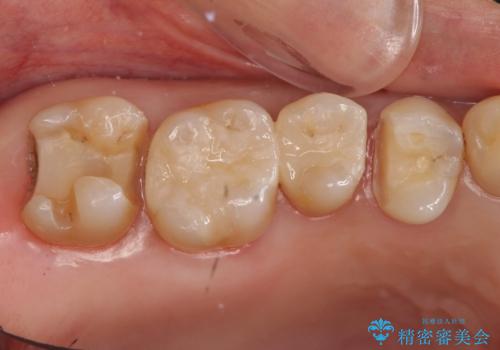

- 虫歯治療を希望して来院。

保険適用の銀色のつめもののやり替えを行いました。

自由診療のインレーの歯型には、シリコンを使用しています。また、処置時には8倍の拡大鏡を用いて、精密に治療しております。